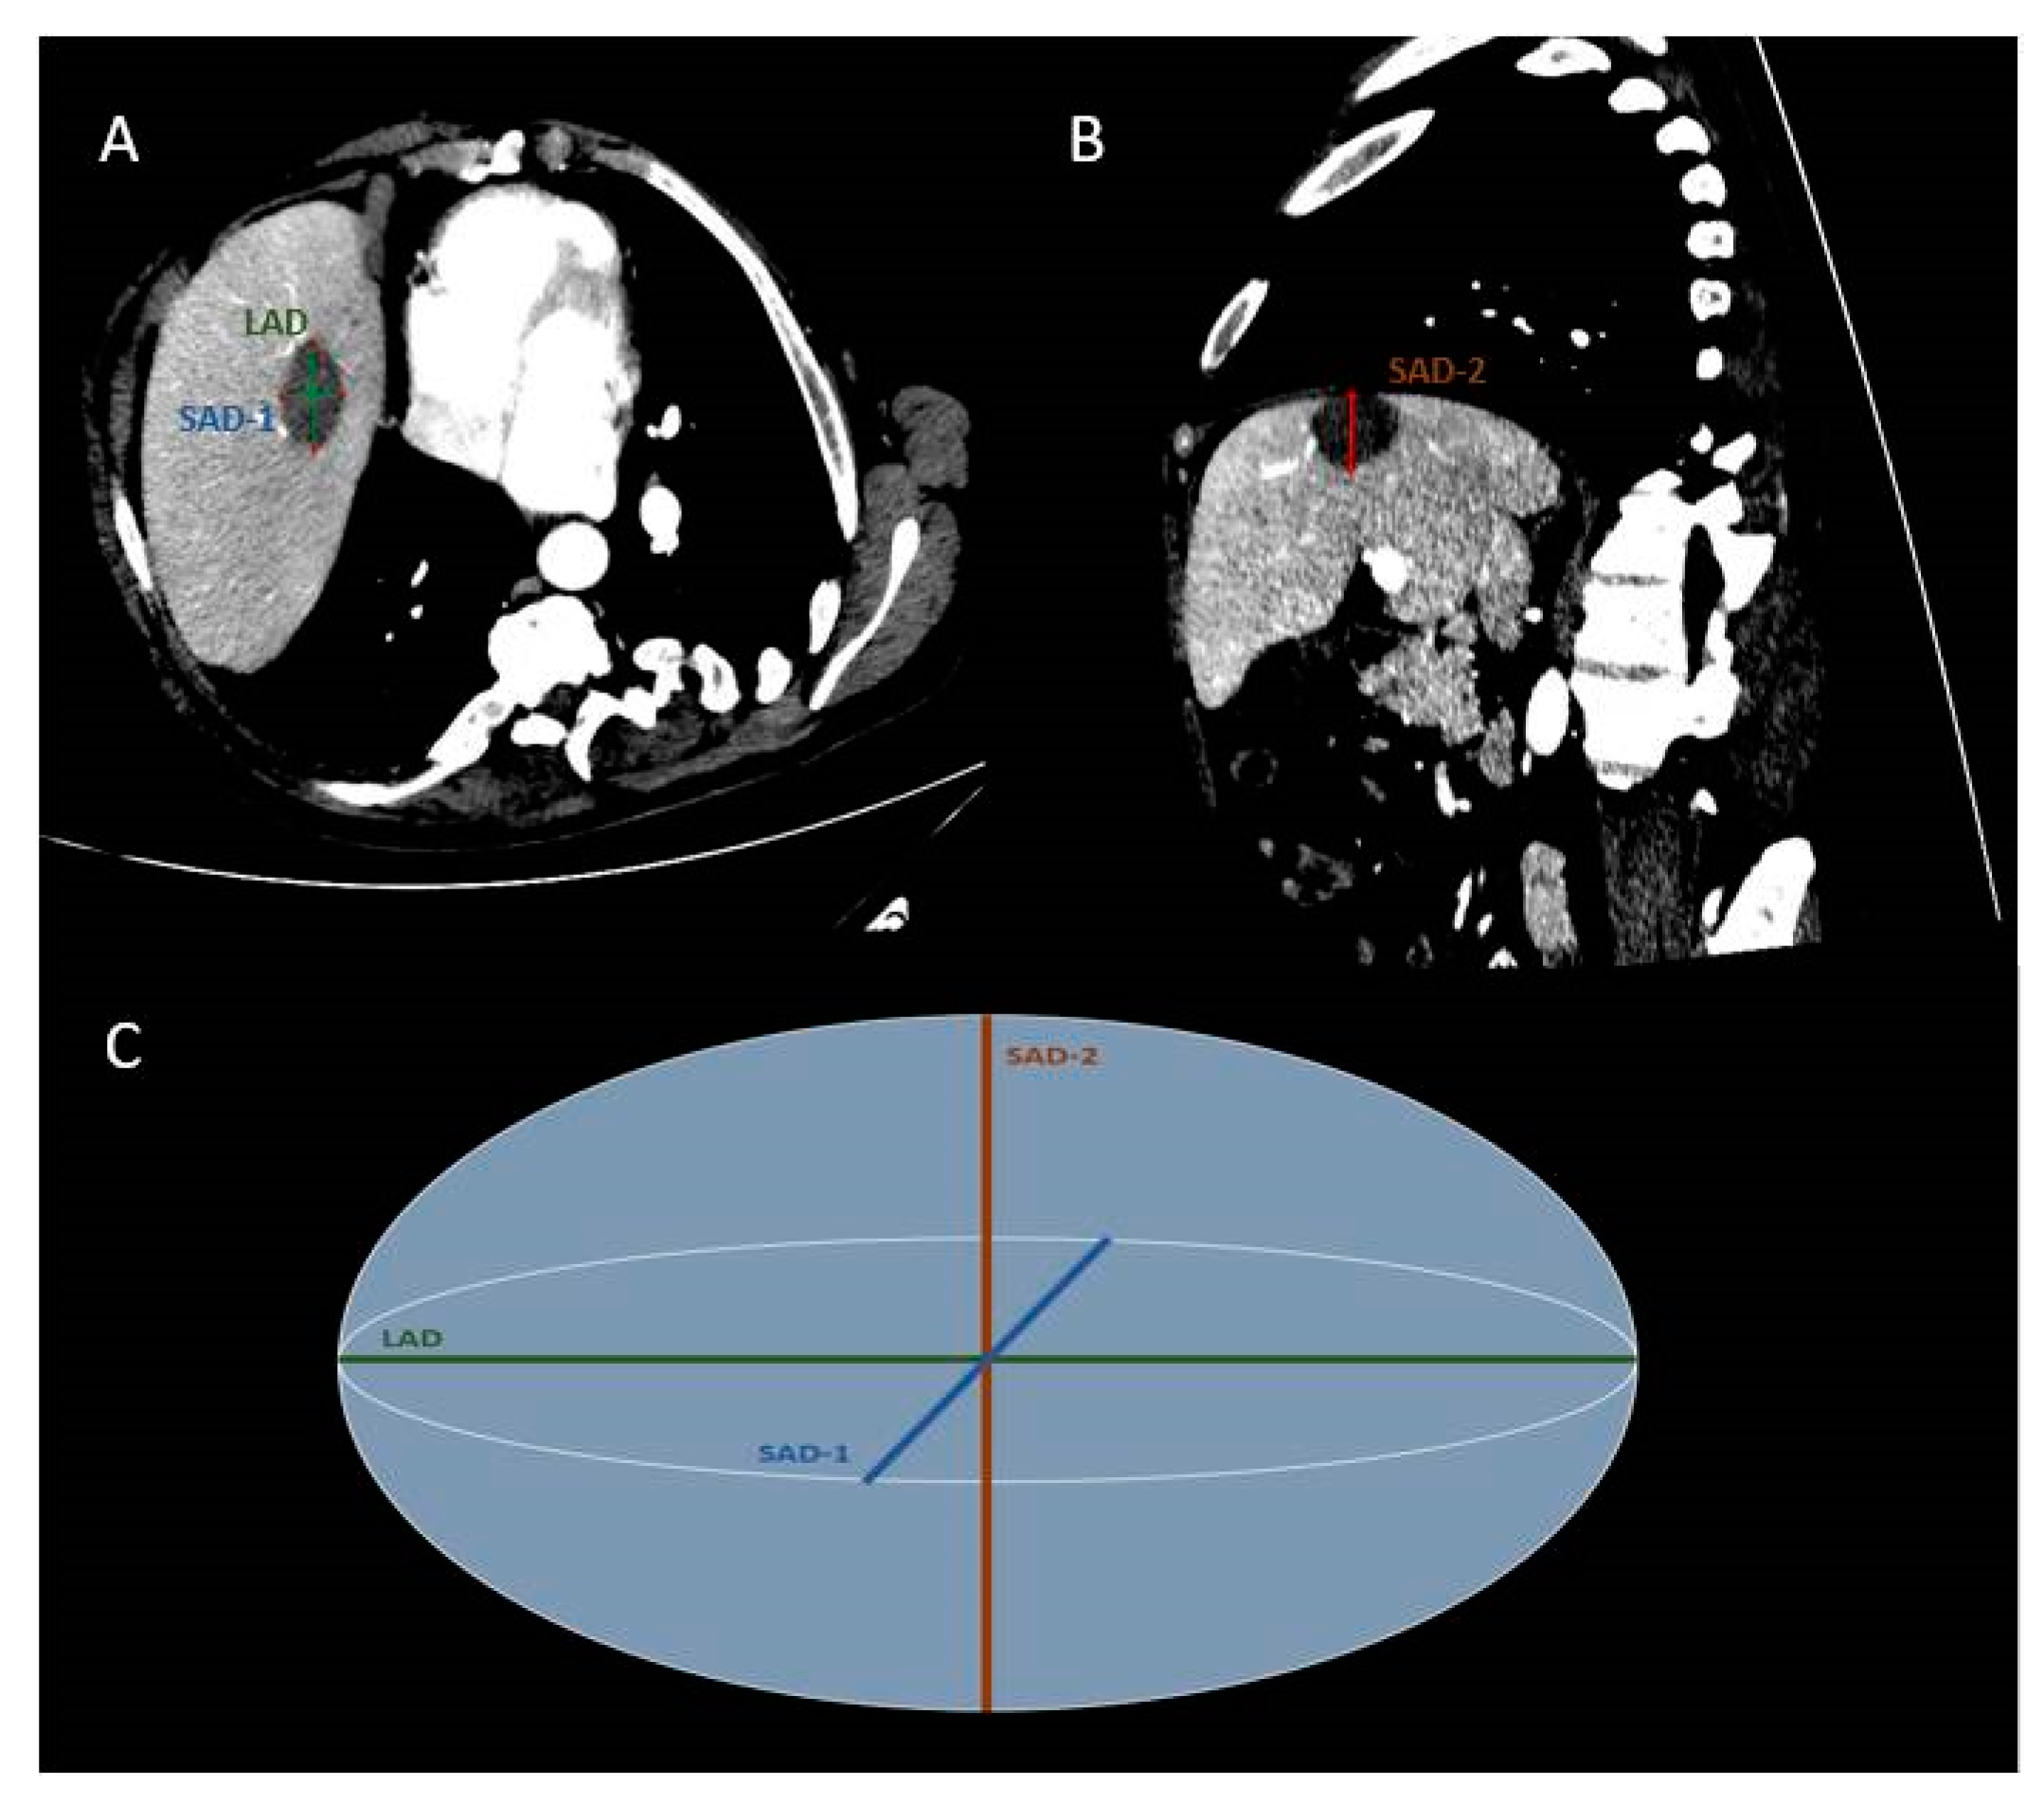

| LAD | 38.76 ± 10.24 (19–60) | 34.31 ± 9.80 (15–55) | 42.37 ± 8.08 (28–66) | 37.29 ± 7.70 (23–62) | F = 2.905, p = 0.092 | F = 31.815, p < 0.001 | F = 2.779, p = 0.100 |

| SAD-1 | 26.67 ± 8.41 (11–46) | 22.69 ± 7.80 (7–40) | 30.03 ± 7.75 (14–45) | 26.29 ± 7.58 (12–42) | F = 5.416, p = 0.023 | F = 25.067, p < 0.001 | F = 0.029, p = 0.864 |

| SAD-2 | 27.69 ± 8.78 (12–45) | 23.76 ± 8.32 (11–40) | 31.86 ± 8.02 (17–48) | 27.80 ± 7.07 (14–45) | F = 6.896, p = 0.010 | F = 16.807, p < 0.001 | F = 0.182, p = 0.671 |

| mSAD | 27.18 ± 8.26 (13.50–45.50) | 23.23 ± 7.73 (11.00–39.50) | 30.94 ± 7.14 (17–46.50) | 27.04 ± 6.74 (15–43.50) | F = 6.943, p = 0.010 | F = 27.376, p < 0.001 | F = 0.038, p = 0.846 |

| mSPH | 0.71 ± 0.13 (0.39–1.00) | 0.68 ± 0.13 (0.36–0.94) | 0.74 ± 0.13 (0.46–1.00) | 0.73 ± 0.15 (0.43–0.98) | F = 3.311, p = 0.073 | F = 1.214, p = 0.274 | F = 4.211, p = 0.044 |